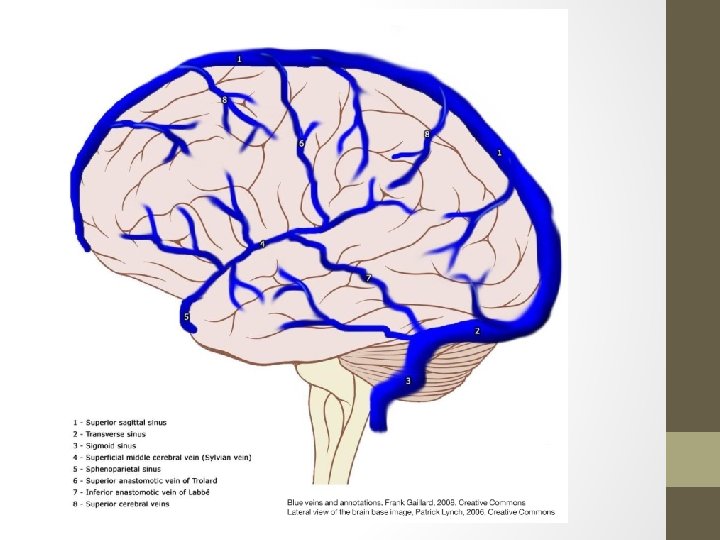

Superficial Venous System • Comprised of the sagittal sinuses and cortical veins. • The cortical veins course along the cortical sulci, drain the cortex and some of the adjacent white matter. • Can be subdivided into superior, middle and inferior groups. • Important veins of superficial cerebral venous system; -Superficial middle cerebral vein -Superior anastomotic vein of Trolard -Vein of Labbé

Superficial Middle Cerebral Vein • Runs along the lateral sulcus-also known as Sylvian Vein • Drains into the sphenoparietal sinus or cavernous sinus • Connected with superior sagittal sinus via great anastomotic vein of Trolard, and with transverse sinus via posterior anastomotic vein of Labbé.